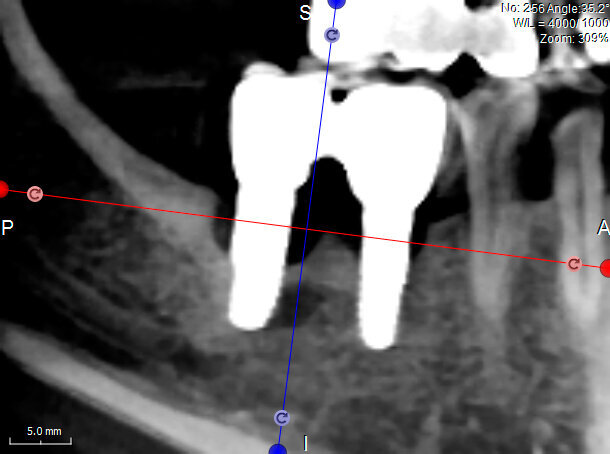

L’innesto è stato protetto con due membrane, opportunamente sagomate e forate per adattarsi attorno a ciascun impianto (Fig. 7). L’operazione è terminata con la sutura dei lembi gengivali tramite filo in poliammide non riassorbibile (Monomyd 4-0, Butterfly, Cavenago) e il posizionamento di due viti di guarigione (Fig. 8). La sutura è stata rimossa a 12 giorni dall’atto chirurgico. Una radiografia di controllo al termine dell’intervento ha confermato l’effettivo ripristino dei volumi ossei perimplantari (Fig. 9). Durante il periodo di guarigione e ai successivi controlli, non si sono osservati segni di sofferenza gengivale (Fig. 10). La paziente non ha lamentato alcuna sintomatologia spontanea o evocata. Al controllo a 3 mesi, l’esame radiografico mostrava il mantenimento dei profili ossei perimplantari (Fig. 11). Sono state quindi rimosse le viti di guarigione e riposizionate le corone.

Al controllo a 15 mesi dall’intervento la paziente non lamenta alcuna sintomatologia e il sanguinamento durante le manovre di igiene orale è scomparso. Eseguita una rx endorale di controllo, si nota un mantenimento ottimale dei livelli ossei e una completa stabilità del contesto perimplantare (Fig. 12).

Fig. 9- Radiografia endorale di controllo al termine dell’intervento.

Fig. 11 - Controllo radiografico a 3 mesi, i livelli perimplantari sono mantenuti.

Fig. 12 - Controllo radiografico a 15 mesi, i livelli perimplantari sono mantenuti.